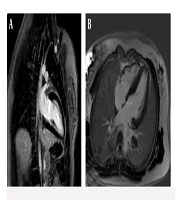

Cardiac Involvement in Friedreich’s ataxia: A Case Series Highlighting Imaging Findings

Mersad MehrnahadORCID,

Hamidreza PouraliakbarORCID,

Fatemeh Abedpour,

Mansoor NamaziORCID*,

Mahya ElmiORCID

|

Final Published